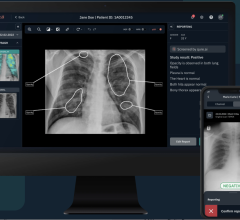

August 7, 2014 — Doctors are gleaning important information from the most common imaging exam, the chest X-ray, by using sophisticated software that improves X-ray images captured by the equipment they already have or are in the process of purchasing. Riverain Technologies revenues increased 34 percent year-over-year through the first half of 2014, based on strong adoption of the company’s ClearRead software solutions. This was particularly true among academic medical centers and community and VA hospitals throughout the Midwest.

Riverain’s ClearRead bone suppression technology helps radiologists detect lung nodules and other serious medical conditions by transforming a traditional chest X-ray into a soft tissue image without the ribs and clavicle bones. These structures commonly obscure abnormalities. There are no additional tests or radiation exposure for patients, and no imaging machines or hardware for the hospital to buy or house to achieve the soft tissue image.

The software is sold directly to medical centers, to enhance X-ray images captured by the machines they already have, and by major manufacturers including Siemens Healthcare and Philips Healthcare as a value-added extension to new X-ray equipment.

University of Chicago Medical Center, U-M Health System, Southern Ohio Medical Center, Riverside Medical Center in Kankakee, Ill., and the Hines VA Hospital in Hines, Ill., are some of the institutions that purchased ClearRead software. University of Chicago did so after serving as a research site and validating the strength of Riverain’s ClearRead Bone Suppression and computer-aided diagnosis (CAD) software, ClearRead +Detect, in improving the diagnostic potential of conventional X-ray images.

ClearRead +Confirm Improves Clarity of Lines, Tubes and Saves Time

In addition to purchasing ClearRead Bone Suppression and ClearRead + Detect software, which marks suspected lung nodules on an X-ray image, U-M Health System physicians are moving forward with purchase of ClearRead +Confirm software based on a clinical evaluation of the software.

ClearRead +Confirm identifies and highlights lines and tubes on portable chest X-ray images, reducing reading time by approximately 19 percent without compromising radiologist accuracy or confidence.

“Referring physicians working in our intensive care units can see lines and tubes much more clearly without having to make adjustments to each image, line-by-line and case by case,” Kazerooni said. “They’re bypassing the standard X-ray image and going directly to the Riverain-processed images. This speaks to how highly they regard the software.”

The benefit of ClearRead +Confirm for patients, Kazerooni added, is that “It gives us greater confidence about the devices we’re putting in place so that we’re sure they’re functioning optimally.”

ClearRead software enhances the expert skills of radiologists to improve patient outcomes using standard chest X-ray, without additional radiation dose or procedures for patients. Riverain ClearRead software solutions include ClearRead Bone Suppression, +Detect, +Confirm and +Compare, which reveals density changes between current and prior chest X-ray images.